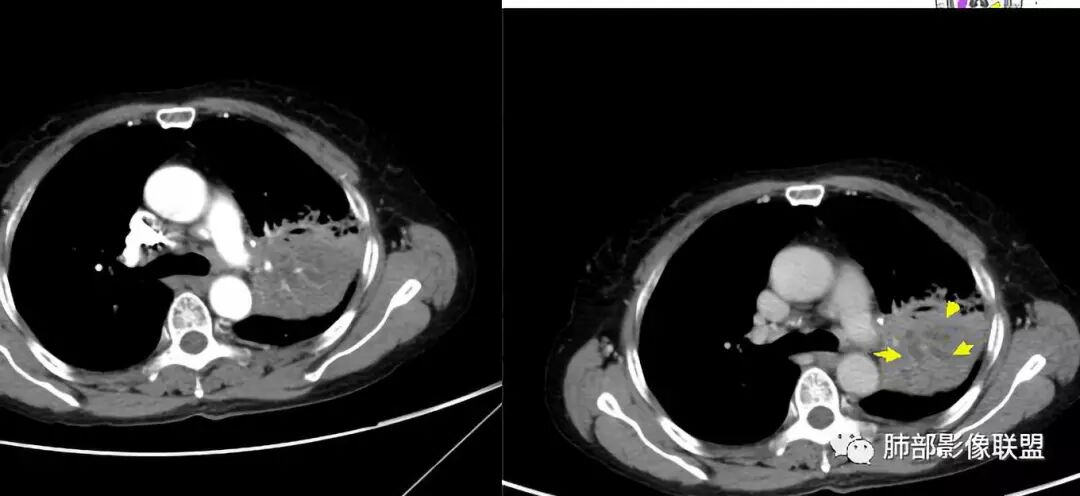

上叶支气管堵塞处稍萎缩、凹陷,附近壁增厚,内可见小点状钙化

树芽征、小叶间隔增厚,淋巴结, 内部血管走形自然

分析:支气管粘液栓、支气管堵塞处萎缩、钙化,支气管通畅处部分扩张,树芽征——提示结核。

看这些钙化

前壁不厚,附近钙化灶太多,所以觉得结核一定要考虑,加上树芽征,就更支持。

支气管因为软骨,密度偏高,从这连续性看,支气管这一段的壁不厚,只是周围有病灶。

支气管壁软骨存在且连续,没有被破坏掉,支气管壁局部通畅,提示支气管壁没破坏,那么近端支气管癌肿不考虑。远端有树丫征,病灶周围很多钙化,所以结核一定有。

结果

电话随访:湘雅医院纤维支气管镜检查:左肺上叶支气管外压狭窄、粘膜病变。穿刺未见肿瘤细胞,考虑结核,抗结核治疗后病情较前好转。

3.支气管阻塞,沿途可见钙化及液性潴留……更符合支气管内膜结核。